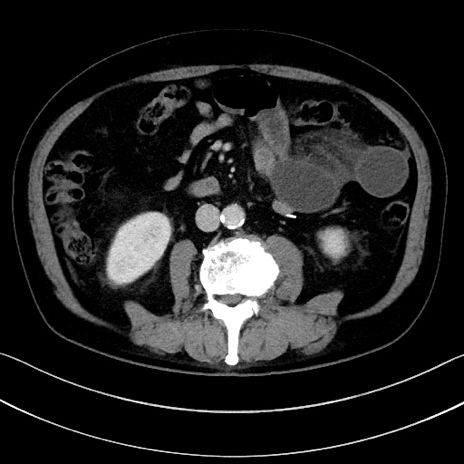

冠状断像

【症例】70歳代男性

【主訴】腹痛

【現病歴】今朝から腹痛あり。全体的に痛い。特に左上の方。排ガスが今日はない。冷や汗が出る。

【既往歴】直腸癌術後

【身体所見】左側腹部〜上腹部に圧痛あり。腹膜刺激症状明らかなではない。軽度反跳痛。左下腹部に術後瘢痕あり。

【データ】WBC 7700、CRP 0.02